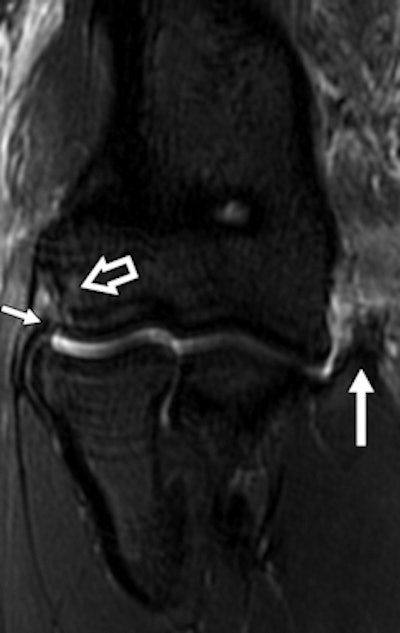

A 30-year-old male judo athlete with valgus stress and hyperextension injury of elbow. Top: Coronal proton density-weighted fat-saturated MRI shows full-thickness tear (white arrow) of proximal humeral attachment of anterior bundle of ulnar collateral ligament (UCL) and edema (black arrow) within surrounding muscle fibers. Below: Axial proton density-weighted fat-saturated MRI shows UCL posterior bundle disruption (long white arrow), with fluid surrounding ulnar nerve (short white arrow). However, ulnar nerve was contiguous on sequential images, with no transection. High-grade tear of flexor carpi ulnaris (black arrow) also was seen. Bottom: Axial proton density-weighted fat-saturated MRI shows high-grade tear of flexor digitorum superficialis (long arrow) and fluid surrounding median nerve (short arrow). All images reprinted with permission from the American Journal of Roentgenology.